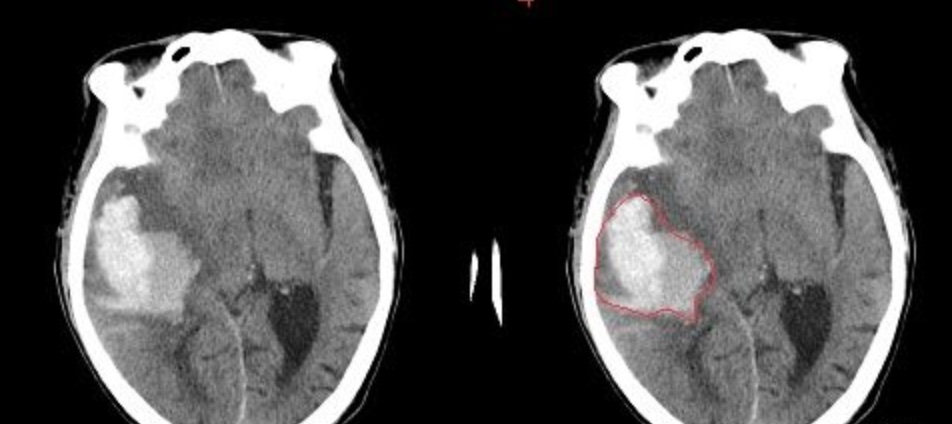

- 1、图像语义较为简单、结构较为固定。比如就用脑CT和脑MRI,由于器官本身结构固定和语义信息没有特别丰富,所以高级语义信息和低级特征都显得很重要(UNet的skip connection和U型结构就派上了用场)。举两个例子直观感受下。

- 脑出血: 在CT影像上,高密度的区域就大概率是一块出血,如下图红色框区域。